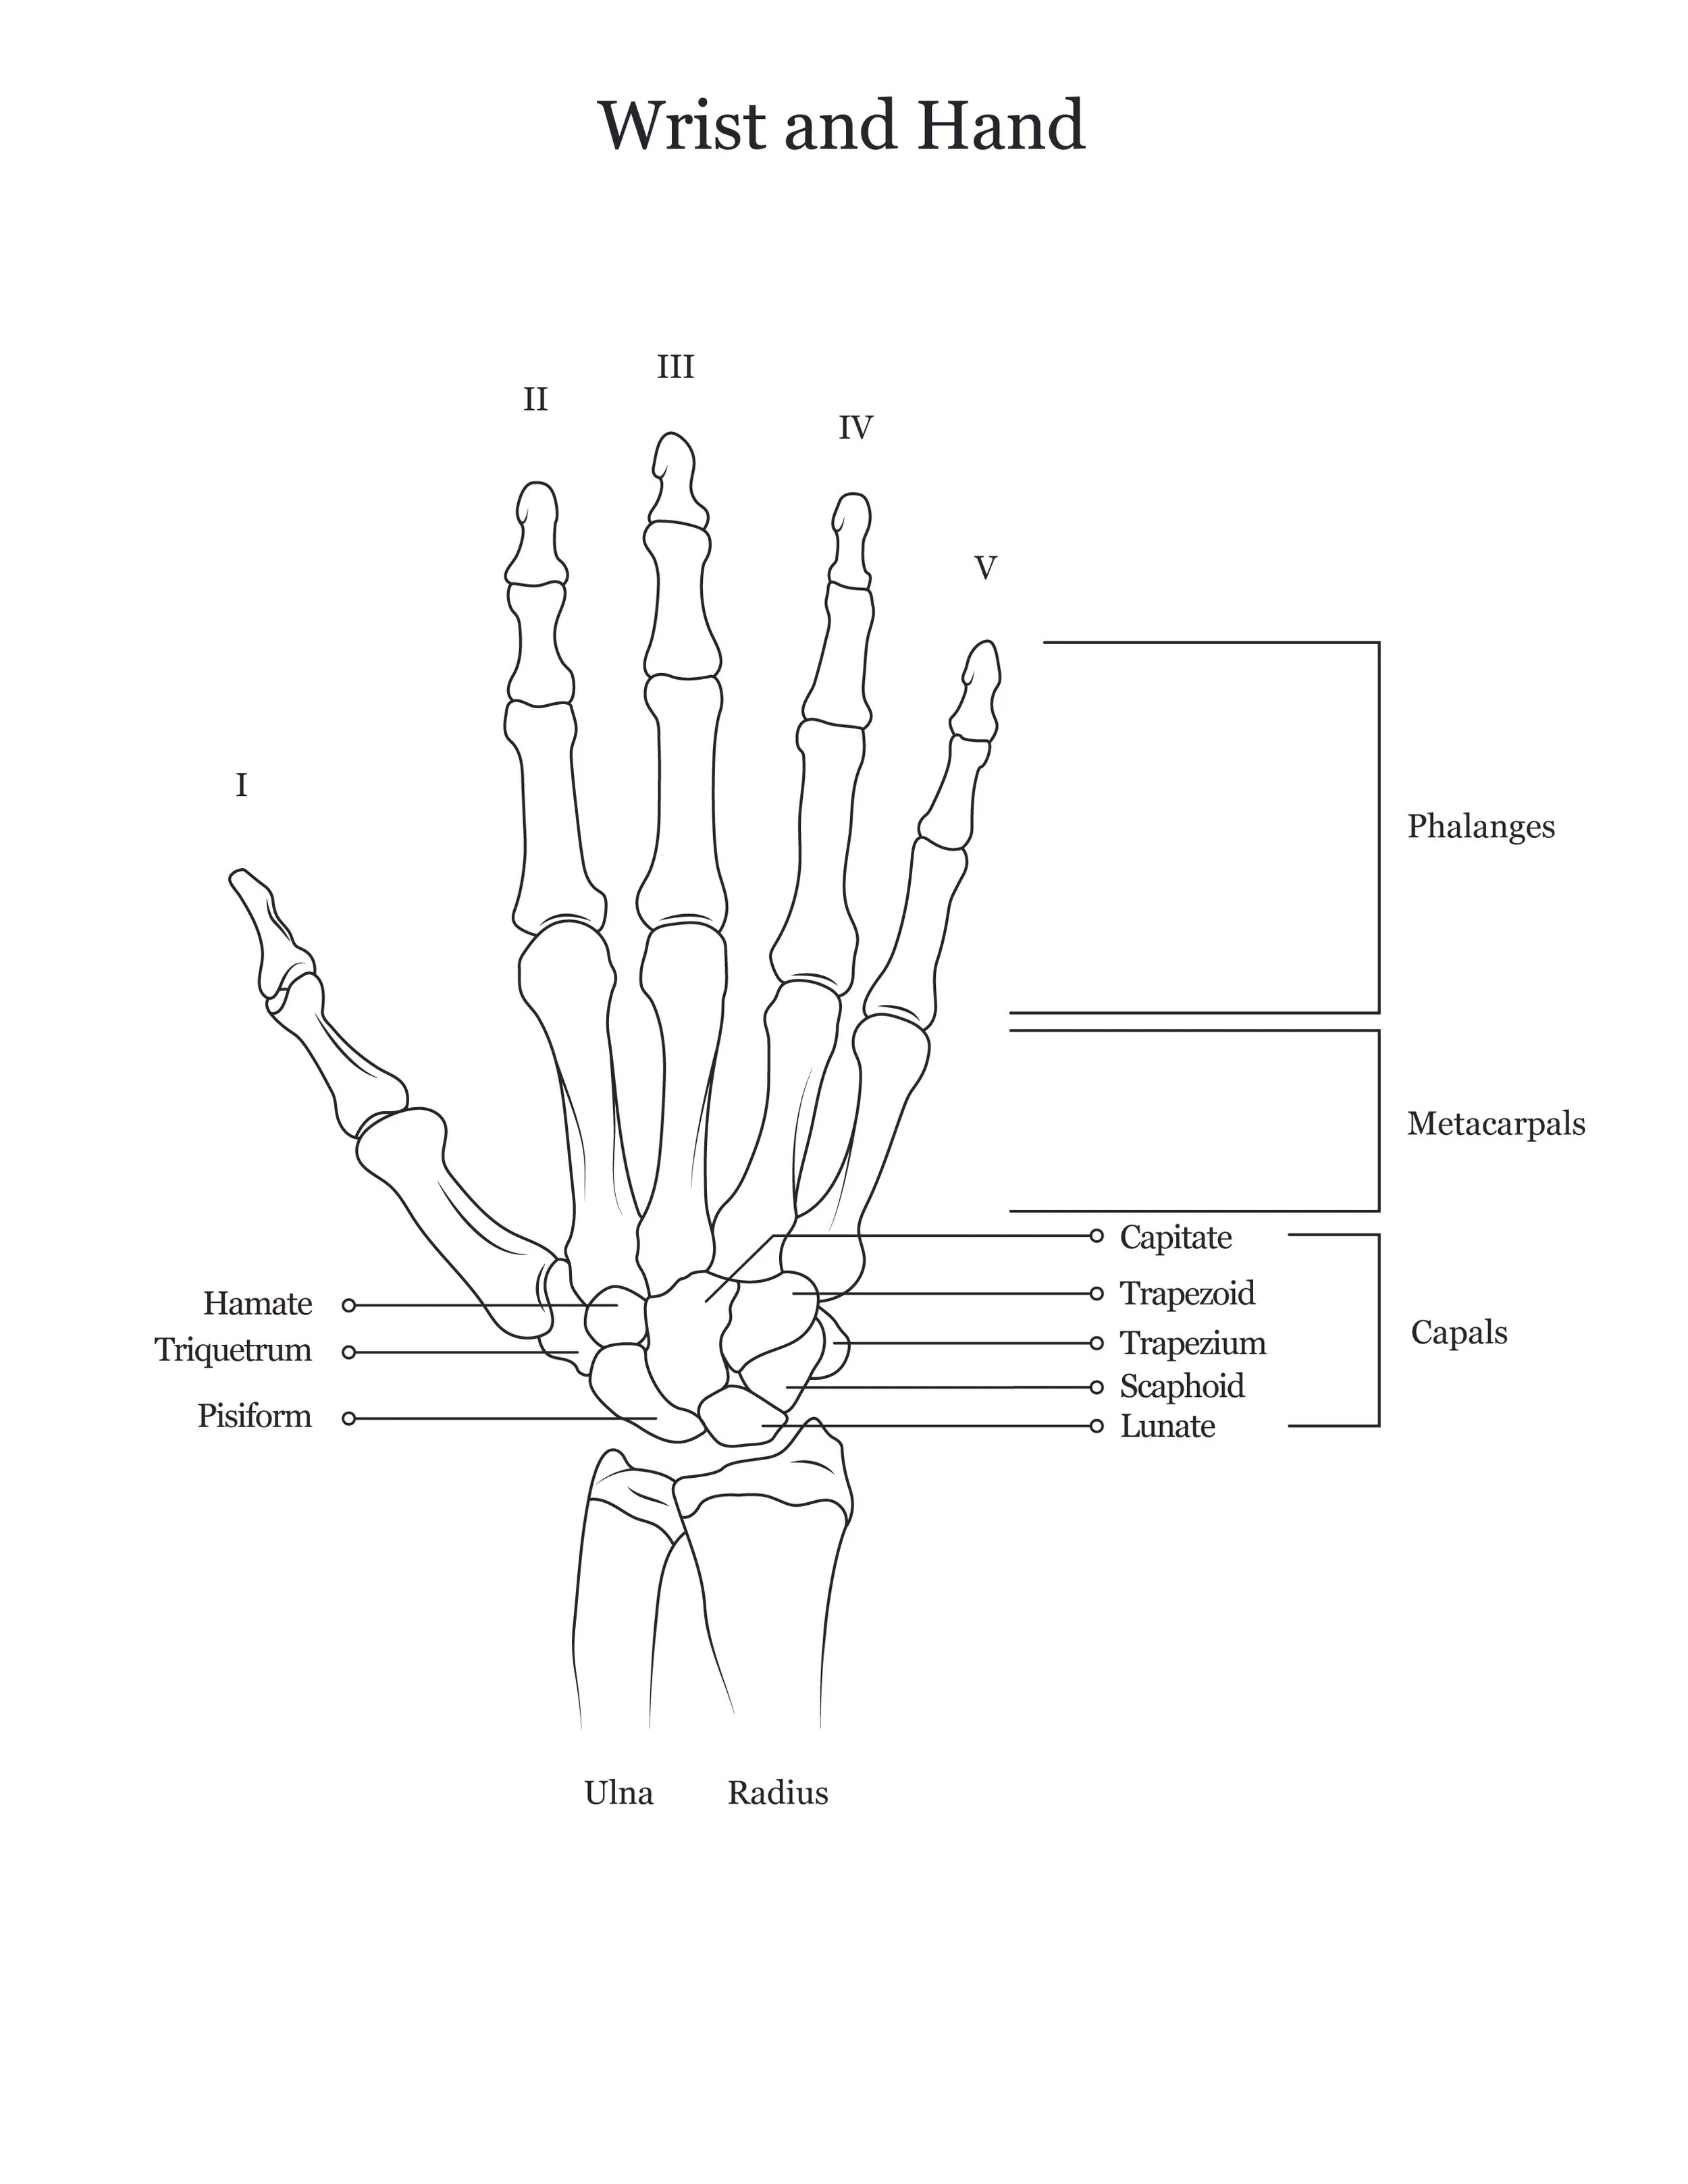

A series of anatomical illustrations created for Arcadia University’s Biology Department.

This project involved illustrating a series of diagrams for a cat dissection manual, focusing on skeletal and muscular anatomy. I consolidated multiple reference sources and firsthand specimen observation into a cohesive visual system for instructional use. Illustrations were refined iteratively to ensure anatomical accuracy, consistency, and clarity for students.